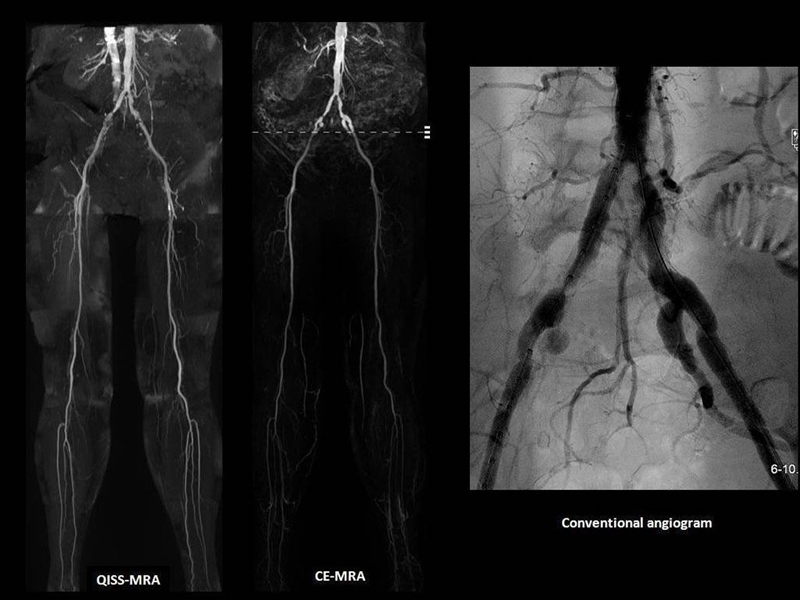

Three types of vascular imaging: QISS-MRA on the left, CE-MRA in the center, and a conventional angiogram on the right.